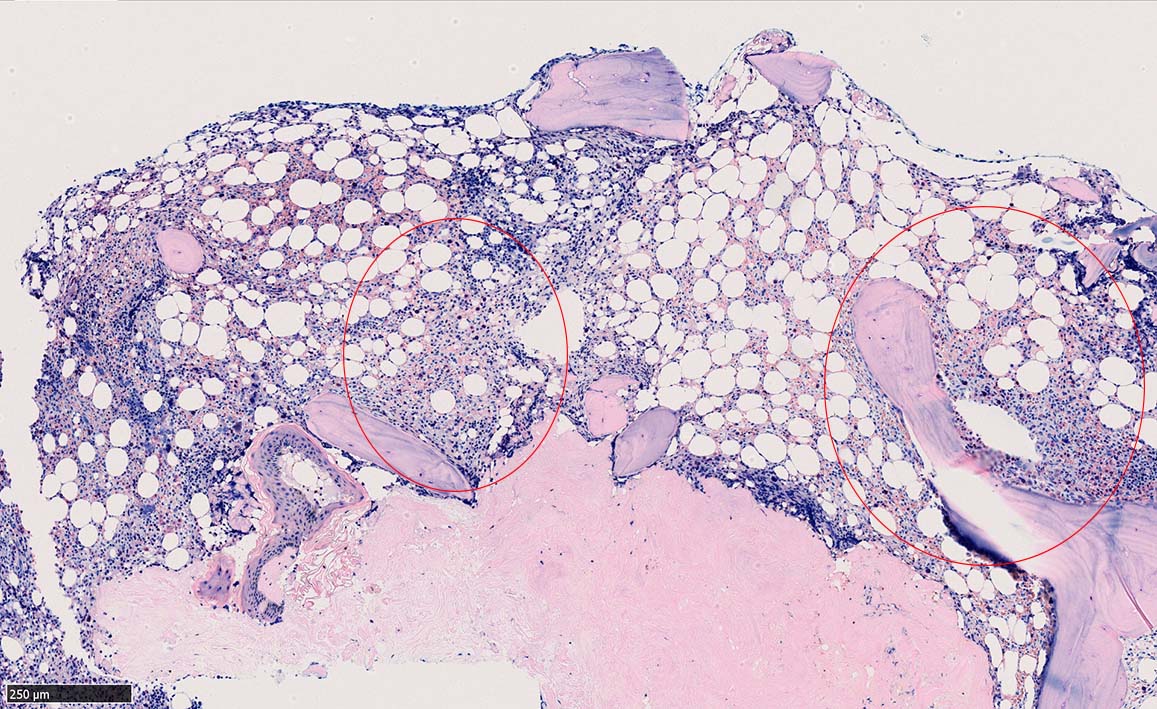

ASD-G 低倍率所見では赤芽球血島は幼若赤芽球の集簇巣が散在する, 顆粒球系細胞(ASDに赤く染色される)は減少,granulopoietic hypoplasiaを呈する.疎な集簇を示すmast cellsの増加がある.

ASD-G陰性の細胞がびまん性に増加しているように見える.

ASD-Giemsa陰性の細胞がシート状に増殖する. 核はクロマチン濃染, 核小体は不明瞭.類円形, 卵円形, くびれを持つ多稜形核, 長円形いびつで屈曲した核, など多彩. 細胞質は淡清色調, 広く淡明. 赤芽球血島は幼若赤芽球のみで形成される異形成像を示す. やや離れて成熟赤芽球が疎な集簇を示す.

Ag染色では, 疎な弾性線維が増生し,増殖細胞を小胞巣状に分画するいわゆる「lymphomatoid pattern」を呈する. 本例では, Mgkに異形成所見がある.